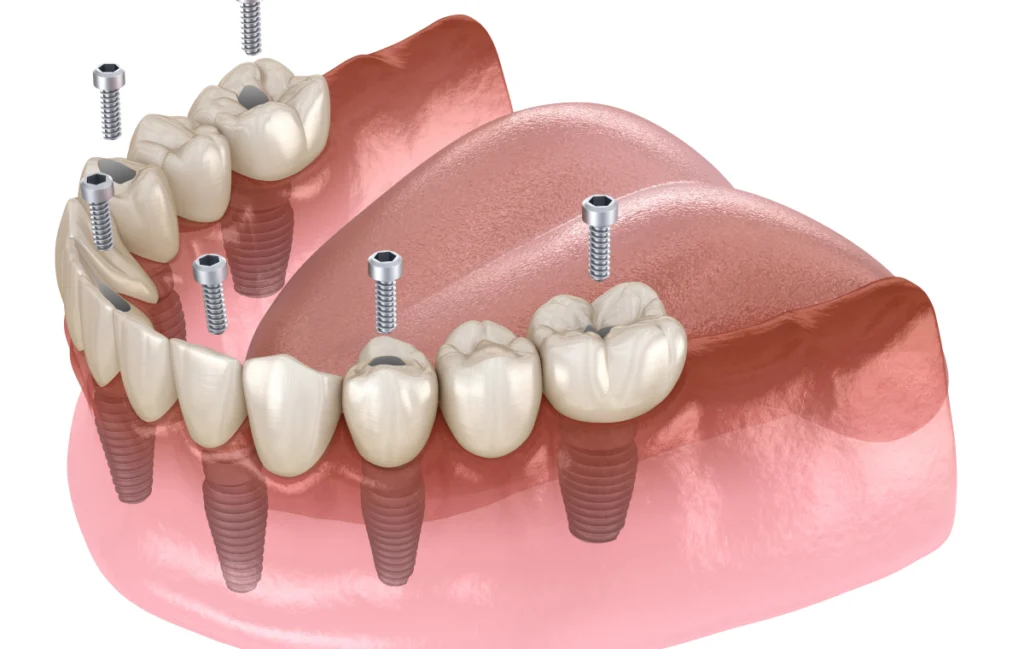

3. Pose des implants

Lors de la phase chirurgicale, le praticien insère les implants dans l’os de la mâchoire avec une grande précision. Selon chaque situation clinique, plusieurs configurations sont possibles :

- Quatre implants peuvent suffire (protocole All-on-4).

- Six ou huit implants peuvent être choisis pour mieux répartir les forces masticatoires.

- Certains implants sont légèrement inclinés afin d’éviter les zones anatomiques sensibles, comme les sinus maxillaires ou le nerf mandibulaire.

6. Pose de la prothèse définitive

Une fois les implants parfaitement intégrés, le praticien procède à la mise en place de la prothèse fixe définitive. Celle-ci est fabriquée sur mesure, afin d’épouser parfaitement la morphologie buccale du patient. Avec un entretien régulier, cette prothèse est conçue pour durer de nombreuses années, tout en offrant une esthétique naturelle et une mastication stable.